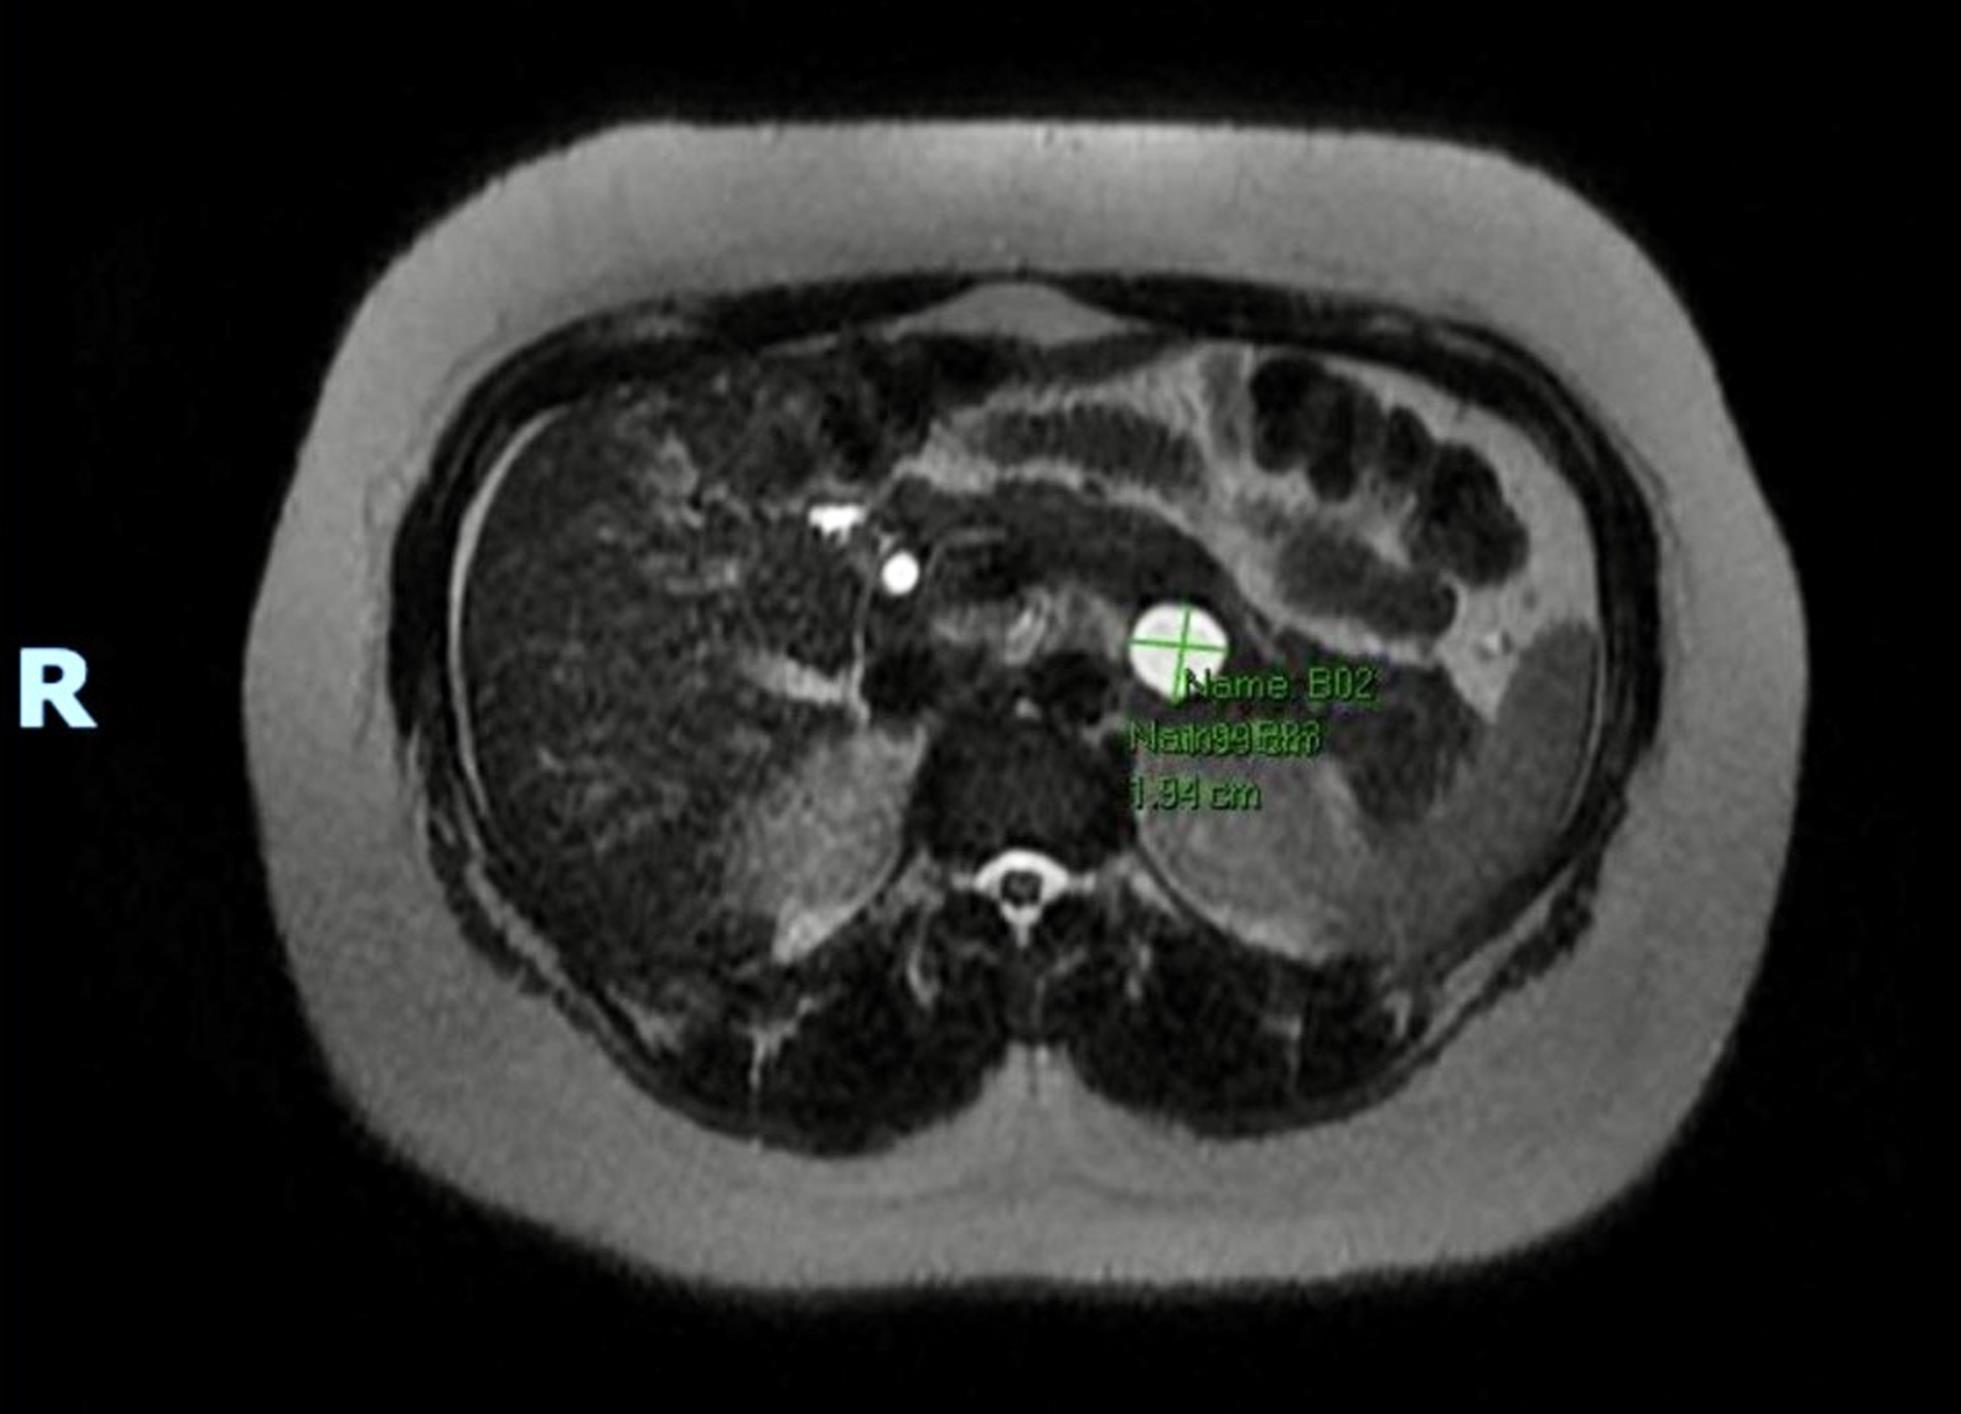

A 32-year-old female with a past medical history significant for asthma, goiter, irritable bowel syndrome, a laparoscopic cholecystectomy in 2020, and a laparoscopic appendectomy in 2022 presented to the emergency room in April 2024 with a severe episode of epigastric pain that had been occurring intermittently over the past several months. CT Abdomen/Pelvis completed on presentation showed a 19 mm cystic focus within the pancreatic tail. An MRI with MRCP, both with and without IV contrast, revealed a cystic lesion in the pancreatic tail measuring up to 2.0 × 1.9 cm. The lesion was characterized by thin peripheral enhancement, with no discernible nodularity, solid mass, or pancreatic ductal dilatation (Fig. 1). This was a significant increase in size from a previous MRI finding in February 2022, which showed dimensions of 0.6 × 0.3 cm (Fig. 2). The patient was further evaluated via EUS with fine needle aspiration (FNA) biopsy. Endosonographic findings confirmed those on MRI and CT, revealing an anechoic lesion measuring 17 mm × 16 mm in maximal cross-sectional diameter with two thinly septated compartments near the junction of the pancreatic tail. There was no associated mass or internal debris within the fluid-filled cavity. Analysis of the components from FNA was non-diagnostic due to scant cellular material, few inflammatory cells, and amorphous material. The overall findings on EUS and FNA were consistent with the MCN of the pancreas. After the endoscopy, the patient underwent an uncomplicated intraoperative resection via robotic spleen-sparing distal pancreatectomy in June 2024. Surgical pathology confirmed a benign MCN with low-grade mucinous epithelium and an ovarian-type stroma, which showed strong diffuse immunoreactivity for CD10 and the progesterone receptor. Gross pathology revealed a 2.1 × 1.1 × 1.0 cm tan-white smooth-lined, clear fluid-filled cyst that had no involvement with the pancreatic duct.

MRI showing initial finding of pancreatic cyst in 2022 with dimensions of 0.6 × 0.3 cm.

Fig. 2  MRI showing initial finding of pancreatic cyst in 2022 with dimensions of 0.6 × 0.3 cm.